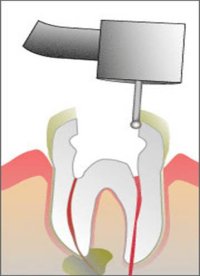

Leczenie kanałowe polega

na usunięciu chorobowo zmienionej miazgi z komory i kanałów zęba oraz ich

odkażeniu i wypełnieniu odpowiednim materiałem, najczęściej cementem i

gutaperką.

Najczęściej leczenie kanałowe wykonuje się w znieczuleniu miejscowym. Pierwszym

etapem jest nawiercenie otworu do komory zęba.

Następnie wiertłem oraz ręcznymi

narzędziami usuwa się martwą i częściowo żywą miazgę zęba początkowo z

komory. Opracowanie komory pozwala mieć lepszy wgląd oraz dostęp do kanałów.

Następnie rozpoczyna się usuwanie chorej miazgi oraz toksyn z kanałów przy

użyciu specjalnych pilniczków, ręcznych czy maszynowych. Używane do tego

są specjalne mikrosilniki edodontyczne o precyzyjnie regulowanych obrotach

z zabezpieczeniem przed przypadkowym zaklinowaniem narzędzia w kanale.

Poszerzanie kanałów polega na użyciu coraz to większych pilniczków tak

by mieć dostęp do kanału na całej jego długości.

Takie opracowywanie kanałów

przebiega z obfitym płukaniem najczęściej podchlorynem sodu.